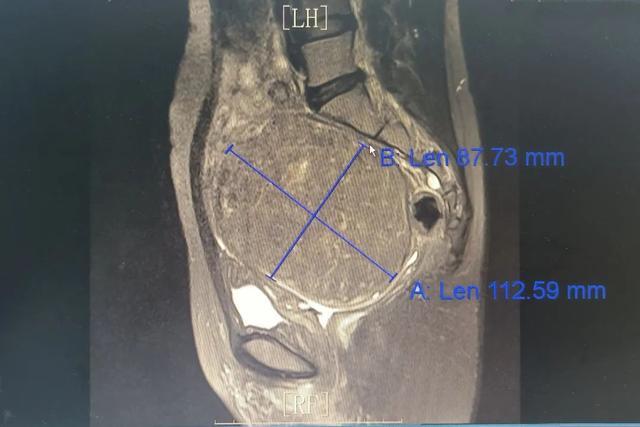

段女士因发现子宫肌瘤3年、尿频3月就诊,完善B超及妇科检查后收住该院妇科,入院完善盆腔核磁检查后确诊为宫颈肌瘤,大小约为11*9*11cm,鉴于患者要求保留子宫且希望进行微创手术,手术团队面临了巨大的挑战。

术中,医生们发现子宫体像一个小不点立在宫颈肌瘤上方,形象地描述为“子宫站在巨人的肩膀上”。